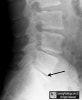

AP, lateral X-ray 검사에서 종종 노화로 인한 퇴행성 변화인 골편, 디스크 높이 감소가 보입니다. 또, 진공징후(vacuum sign)로 인해 디스크 내 공기(질소)가 보이기도 합니다.

X-ray : 진공징후(vacuum sign)